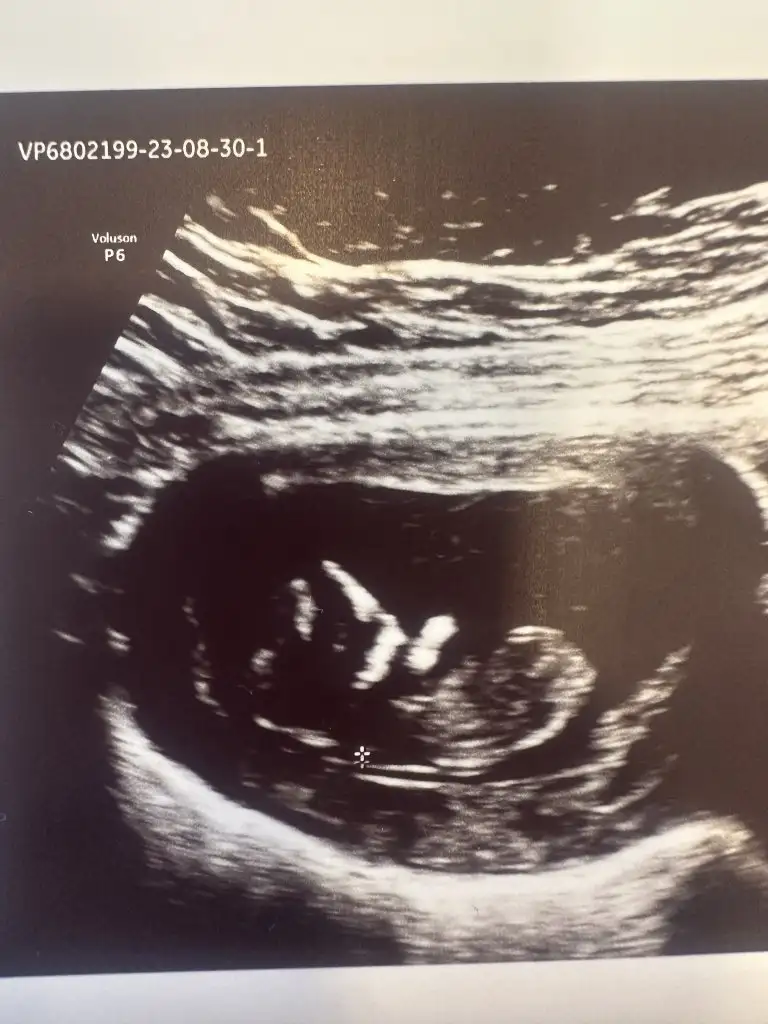

Arkadaslar benimde bebegimin cinsiyetinde bir tahmininiz var mi? Ramzi teorisine göre bakabilen varsa memnun olurum

11+5 haftalik karindan